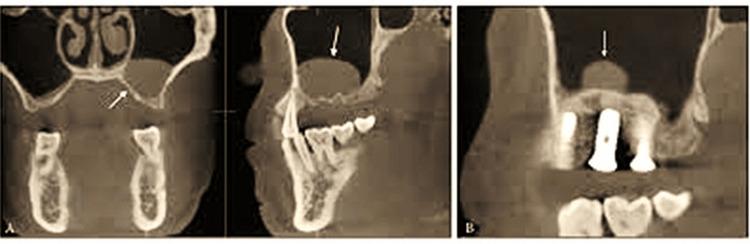

Background To achieve a better long-term prognosis in the posterior maxilla with poor quality of bone, the sinus lift must ensure bone regeneration till the apex of the dental implant for osseointegration. An indirect sinus lift is a minimally invasive procedure where simultaneous bone condensation is achieved. During the sinus lift procedures, different graft materials are used to gain the height of the bone in the sinus. The present study aimed to evaluate the outcomes of indirect sinus lift with hydraulic pressure and the simultaneous placement of implant using platelet-rich fibrin (PRF). Methodology In total, 24 subjects aged 18-74 years with missing maxillary premolars and first and second molars who opted for dental implants placed with indirect sinus lift with hydraulic pressure and had low sinus with less residual ridge height, bone density, and bone height were assessed at one day, one week, one month, three months, and six months. Results The average mean height preoperatively was 5.573 ± 0.66 mm which showed a significant increase postoperatively to 9.603 ± 0.78 mm (p < 0.001). Mean sinus membrane lift was 4.8 ± 2.2 mm at six months. The implant stability quotient increased significantly at six months postoperatively from 69.07 ± 3.39 at the immediate postoperative time to 72.92 ± 2.714 at six months postoperatively (p < 0.001). Conclusions The current study suggests that minimally invasive indirect sinus lift with bone augmentation utilizing PRF increased residual alveolar ridge height and implant stability with fewer problems than previous sinus lift procedures in the posterior maxillary area.

为了在骨质量较差的上颌后牙区获得更好的长期预后,上颌窦提升术必须确保骨再生直至牙种植体根尖以实现骨结合。间接上颌窦提升术是一种微创操作,可同时实现骨压缩。在上颌窦提升术中,使用不同的移植材料来增加上颌窦内的骨高度。本研究旨在评估水压间接上颌窦提升术及同期使用富血小板纤维蛋白(PRF)植入种植体的效果。方法:总共评估了24名年龄在18 - 74岁之间、上颌前磨牙及第一和第二磨牙缺失且选择采用水压间接上颌窦提升术植入种植体、上颌窦较低且剩余牙槽嵴高度、骨密度和骨高度较低的受试者,分别在术后1天、1周、1个月、3个月和6个月进行评估。结果:术前平均高度为5.573±0.66毫米,术后显著增加至9.603±0.78毫米(p<0.001)。6个月时平均上颌窦膜提升高度为4.8±2.2毫米。种植体稳定性商数在术后6个月从术后即刻的69.07±3.39显著增加至72.92±2.714(p<0.001)。结论:本研究表明,利用PRF进行骨增量的微创间接上颌窦提升术可增加上颌后牙区剩余牙槽嵴高度和种植体稳定性,且比以往的上颌窦提升术问题更少。